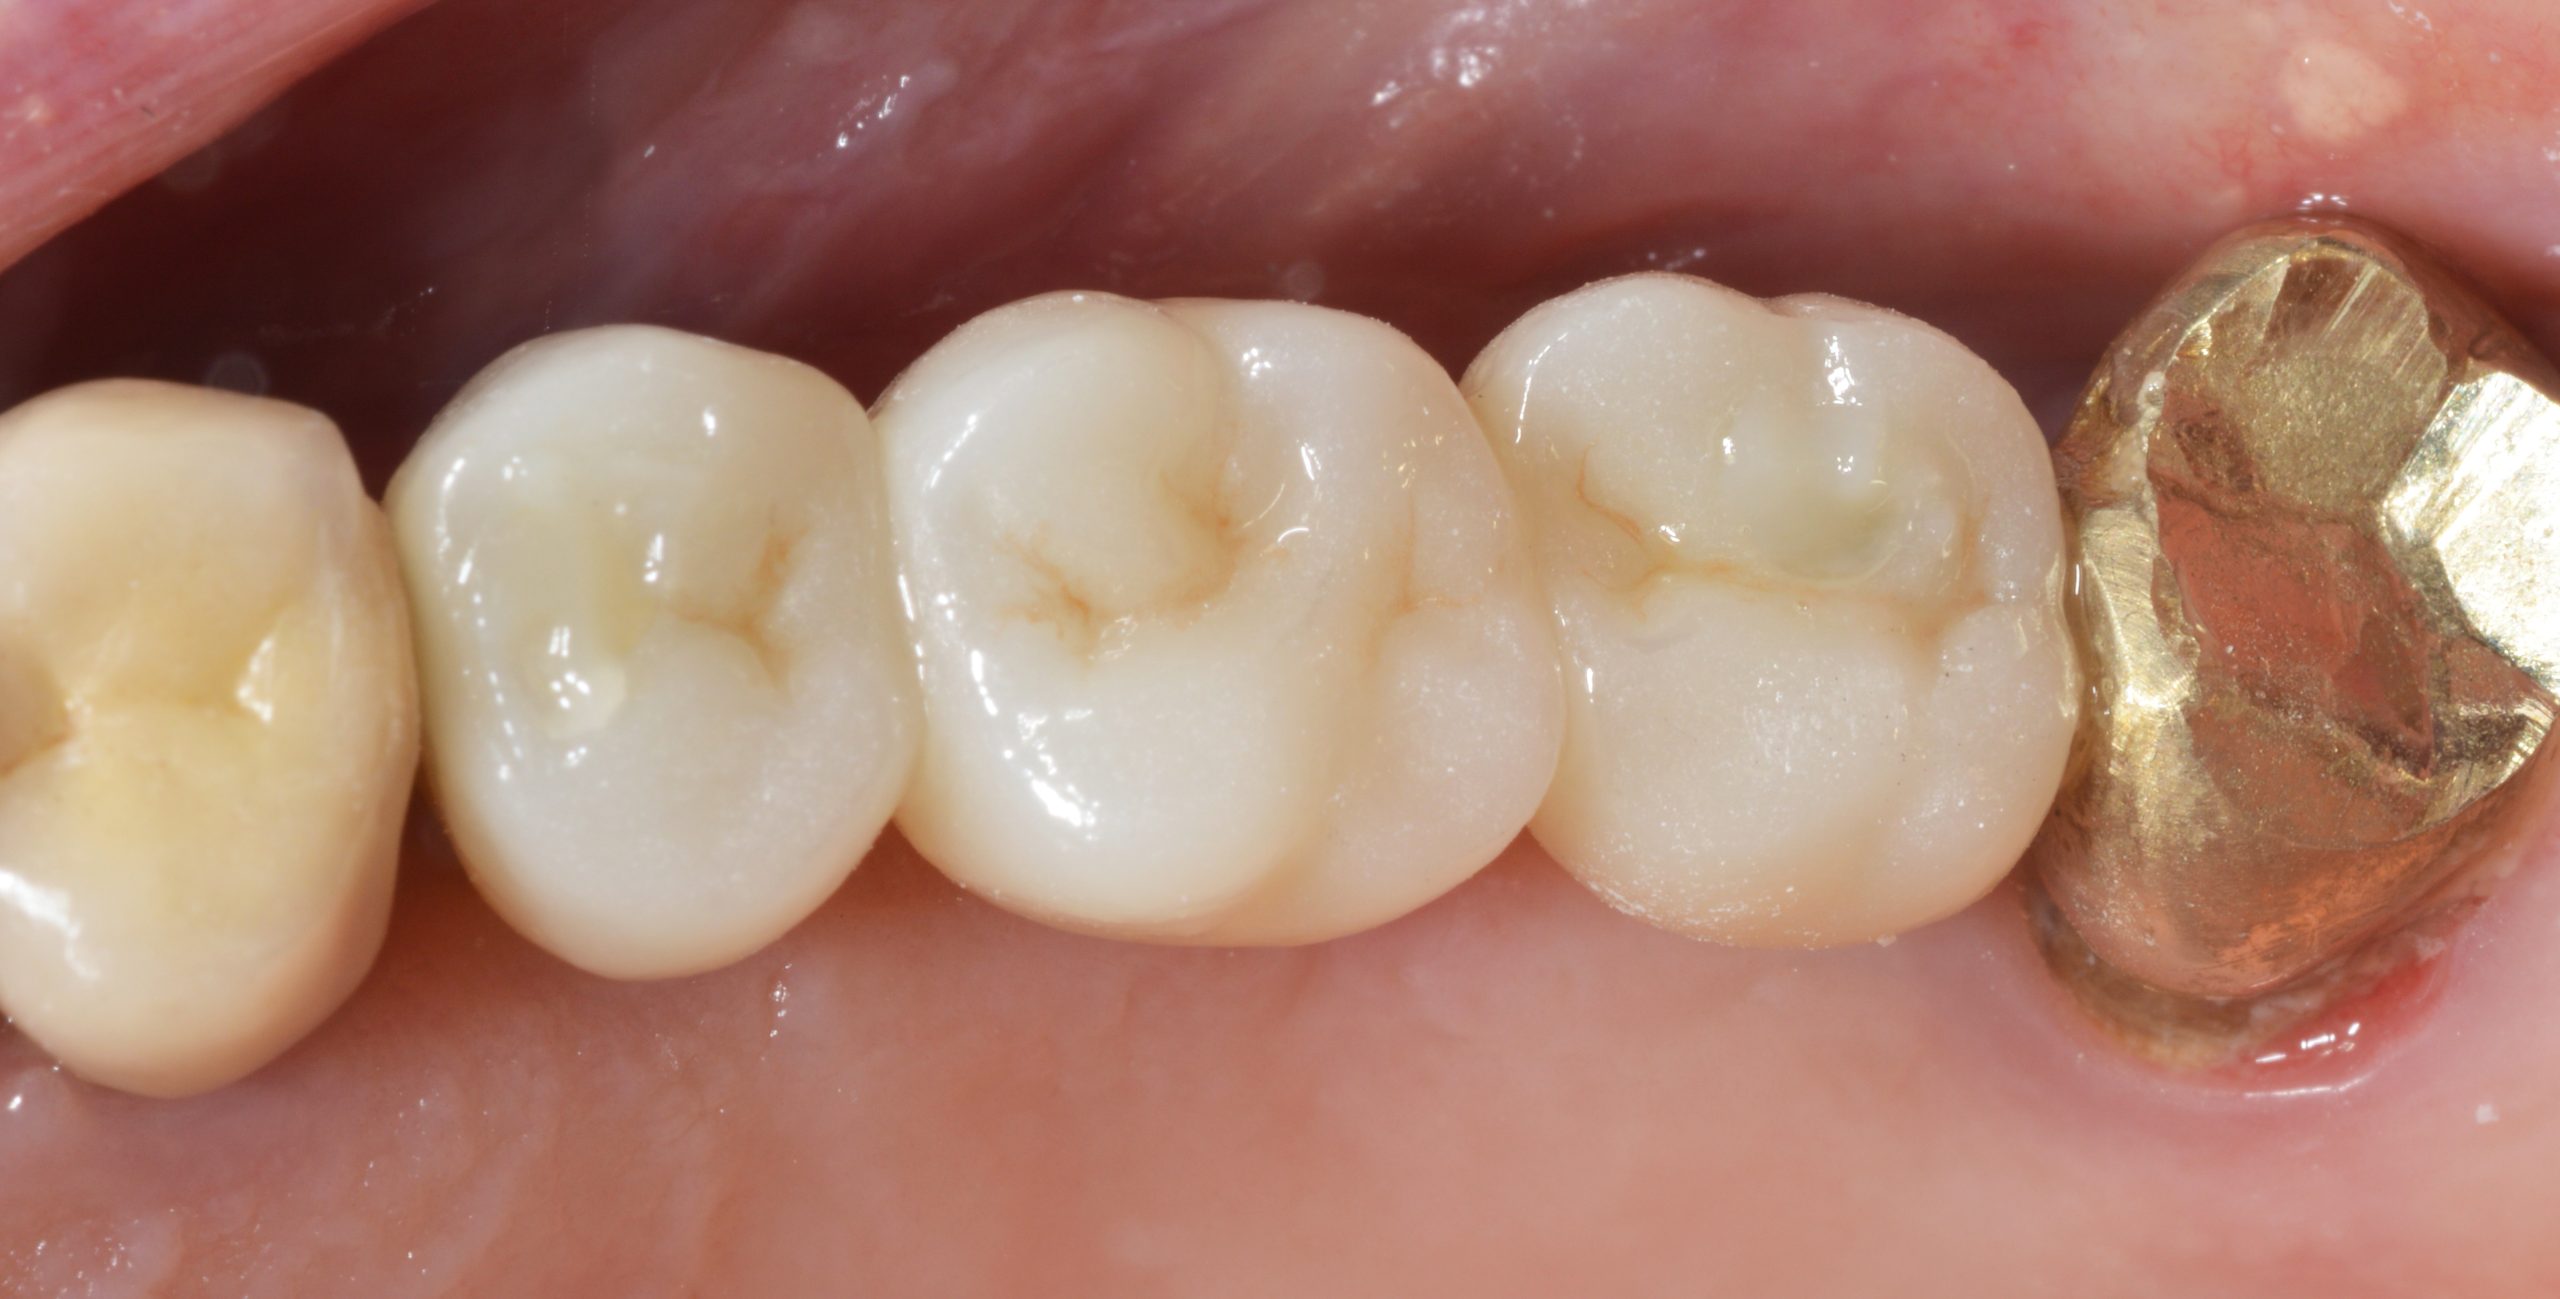

Excellent fit and functional as well as highly esthetic result. The final prosthesis was placed five months after implant placement. The occlusal screw openings were “service-friendly” sealed with composite.

Good soft tissue stability is also evident 23 months after implant placement. Satisfactory cleaning also contributes to this.